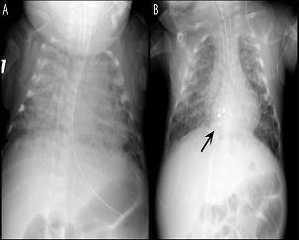

Fig. 1. A la izquierda, en A, se muestra la radiografía del lactante en el momento de su presentación, que demuestra congestión vascular pulmonar con cardiomegalia. A la derecha, en B, radiografía de tórax 24 horas después de la implantación del dispositivo en la CIA (flecha negra), observándose la resolución significativa de la congestión muscular pulmonar y de la cardiomegalia.

INFORME DEL CASOSe remitió a la institución de los autores un lactante de 112 días de vida con una historia clínica de 23 semanas de embarazo y un peso al nacer de 700 g por la incapacidad para desconectarle del ventilador y una cardiopatía congénita complicada. El lactante era producto de un embarazo gemelar cuyo hermano murió posteriormente debido a las complicaciones de la prematuridad extrema. Previamente, en el curso clínico del lactante se había diagnosticado una persistencia del conducto arterioso, al igual que una CIA. Después del fracaso del tratamiento médico, se procedió a la ligadura quirúrgica del conducto arterioso. El lactante se había sometido a un período prolongado de soporte ventilatorio con oscilación de alta frecuencia y, antes de su traslado, no había sido posible desconectarle del ventilador. En el momento del traslado, el lactante permanecía ventilado con ajustes de ventilación moderados con una hipercarbia y necesidades de oxígeno significativas, estableciéndose un diagnóstico de enfermedad crónica pulmonar, es decir, displasia broncopulmonar (fig. 1a). Es de destacar que el lactante tenía antecedentes de hemorragia intraventricular.

En el momento del procedimiento, el peso del lactante era de 2,3 kg. Con el lactante sedado y paralizado, respirando un 35% de oxígeno, se obtuvo un acceso vascular femoral y se efectuó un cateterismo cardíaco derecho e izquierdo anterógrado. Mediante pulsioximetría, se puso de relieve un cortocircuito izquierda a derecha significativo, con un cociente de flujo pulmo-nar/sistémico mayor que 3, hipertensión pulmonar y desaturación venosa pulmonar. Además, se identificó un aumento de las presiones diastólicas ventriculares derechas con insuficiencia cardíaca derecha a partir de la sobrecarga de volumen. Durante el procedimiento, el lactante recibió heparina (100 U/kg) y cefazolina (25 mg/kg). Se modeló un catéter Arrowflex de 22 cm y calibre 6 (Arrow International Reading, MA) para acceder perpendicularmente al tabique auricular, y se hizo avanzar desde la vena femoral. La ecocardiografía transtorácica simultánea demostró un diámetro no desplegado del defecto de 5,5 mm, y un cortocircuito izquierda a derecha (fig. 2a). Se seleccionó un dispositivo Amplatzer Septal Occluder de 6 mm (AGA Medical Golden Valley, MN) y se desplegó a través del defecto. Con el cable de distribución todavía unido al dispositivo, se observó un desplazamiento caudal significativo del tabique auricular. Sin embargo, la ecocardiografía demostró que el dispositivo se asentaba apropiadamente con el tejido septal auricular capturado entre su parte auricular izquierda y derecha (fig. 2b). Tras la liberación del dispositivo del cable de distribución, tanto aquél como las estructuras cardíacas recuperaron una orientación más normal. Al cabo de 24 horas, la radiografía de tórax demostró una mejora sustancial de la congestión pulmonar y la normalización de la cardiomegalia (fig.1b). El lactante pudo desconectarse rápidamente del ventilador emprendiendo la extubación a los tres días del procedimiento.